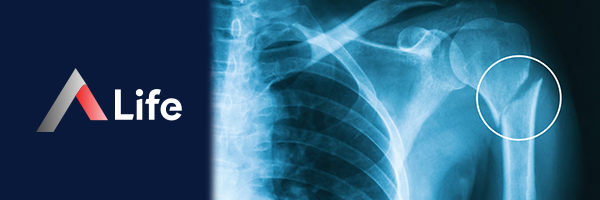

• Omuz Çıkığı: Omuz eklemi çıkığı, skapulanın glenoid kavitesinden humerus başının çıkmasıdır. Bu durum, şiddetli ağrı, deformite ve hareket kaybına neden olur. Tedavi, eklemin yerine oturtulması ve ardından fizik tedaviyi içerir.

• Humerus Baş Nekrozu: Humerus başının kan dolaşımının bozulması sonucu kemik dokusunun ölmesidir. Bu durum, ağrı ve hareket kısıtlılığına neden olur. Tedavi, ilaçlar, fizik tedavi veya cerrahiyi içerebilir.

Humerus Üst Uç Kırığı​

Humerus üst uç kırığı, kol kemiğinin omuz eklemine yakın olan üst kısmında meydana gelen kırıklardır. Bu kırıklar, genellikle yaşlılarda düşme sonucu veya gençlerde yüksek enerjili travmalar (trafik kazaları, spor yaralanmaları gibi) sonucu oluşur.

Humerus üst uç kırıkları, kırık çizgisinin yerine ve kemik parçalarının sayısına göre farklı tiplerde sınıflandırılır. Neer sınıflandırması, en sık kullanılan sınıflandırma sistemidir ve kırıkları 4 parçaya ayırır:

• Tek Parça Kırığı: Kemikte sadece bir kırık çizgisi vardır ve parçalar yerinden oynamamıştır.

• İki Parça Kırığı: Kemik iki parçaya ayrılmıştır ve parçaların biri yerinden oynamıştır.

• Üç Parça Kırığı: Kemik üç parçaya ayrılmıştır ve parçaların ikisi yerinden oynamıştır.

• Dört Parça Kırığı: Kemik dört veya daha fazla parçaya ayrılmıştır ve tüm parçalar yerinden oynamıştır.

Humerus üst uç kırığı tedavisi, kırığın türüne, yerine, şiddetine ve hastanın yaşına ve genel sağlık durumuna bağlı olarak değişir.

• Konservatif Tedavi:

• Kol Askısı: Tek parça veya hafif yer değiştirme olan kırıklarda, kol askısı ile tedavi yeterli olabilir.

• Fizik Tedavi: İyileşme sürecinde, kolun hareketliliğini ve gücünü geri kazanmak için fizik tedavi uygulanır.

• Cerrahi Tedavi:

• Kapalı Redüksiyon ve Fiksasyon: Kırık parçaları yerinden oynamışsa, kapalı yöntemle yerine oturtulup vidalar, teller veya plaklar ile sabitlenebilir.

• Açık Redüksiyon ve Fiksasyon: Daha karmaşık kırıklarda, açık cerrahi ile kırık parçaları yerine oturtulup sabitlenir.

• Omuz Protezi: Çok parçalı kırıklarda veya yaşlı hastalarda, omuz eklemi protezi uygulanabilir.

humerus___st_u___k__r__________54606056.webp